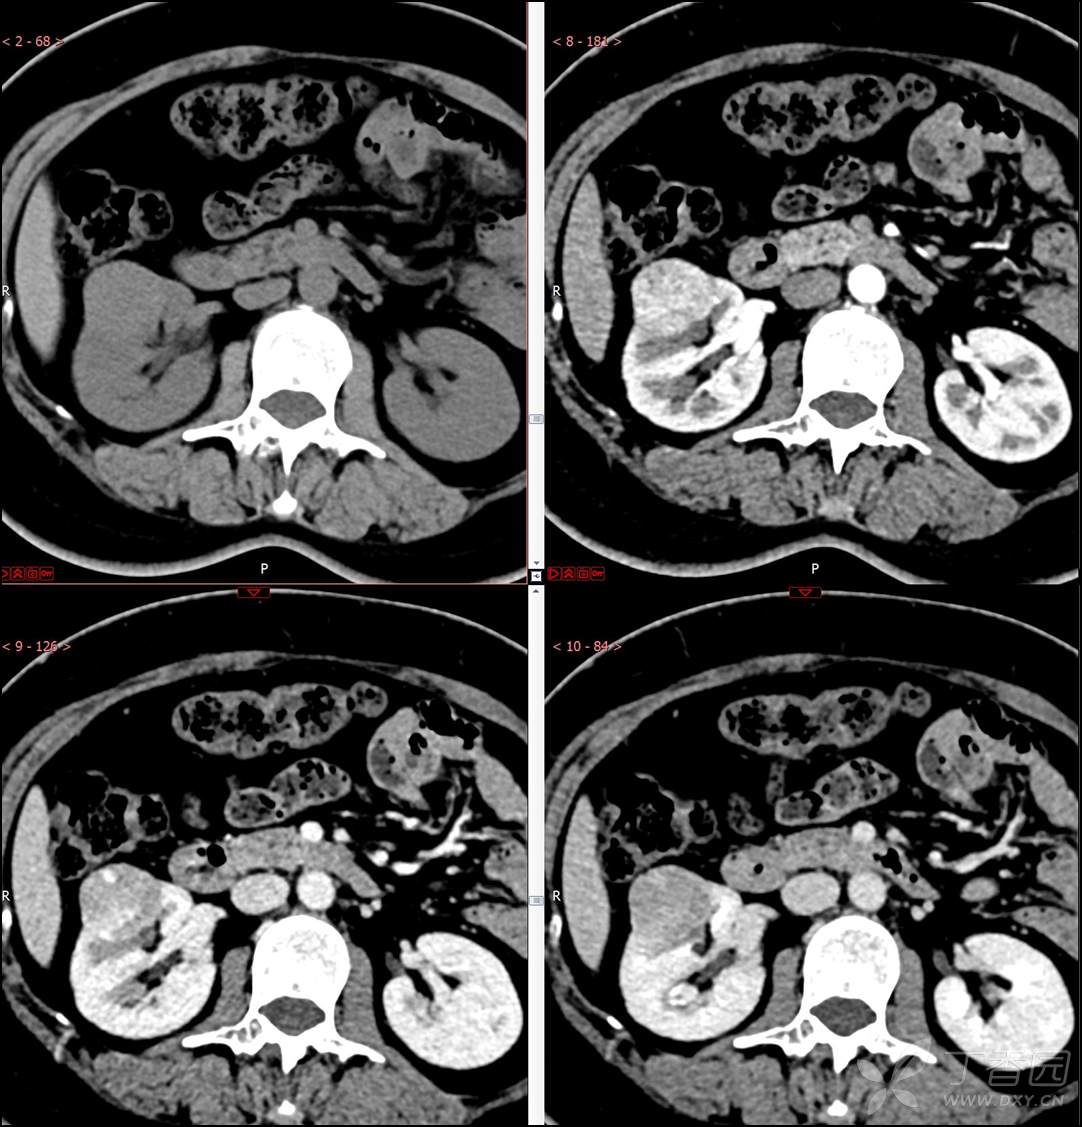

【影诊笔记516】中年女性,检查发现肾占位2周就诊~『嗜酸细胞腺瘤』

主诉:检查发现肾占位2周

简要病史:患者2周前体检发现肾实质性占位,无腰痛,无血尿,无尿频、尿急、尿痛,无发热,在外未行特殊治疗。患者为行进一步治疗就诊于我院,门诊以“肾占位性病变 ”收入我科,患者自发病以来,神志清,精神可,小便如上所述,大便正常,体重无显著变化。